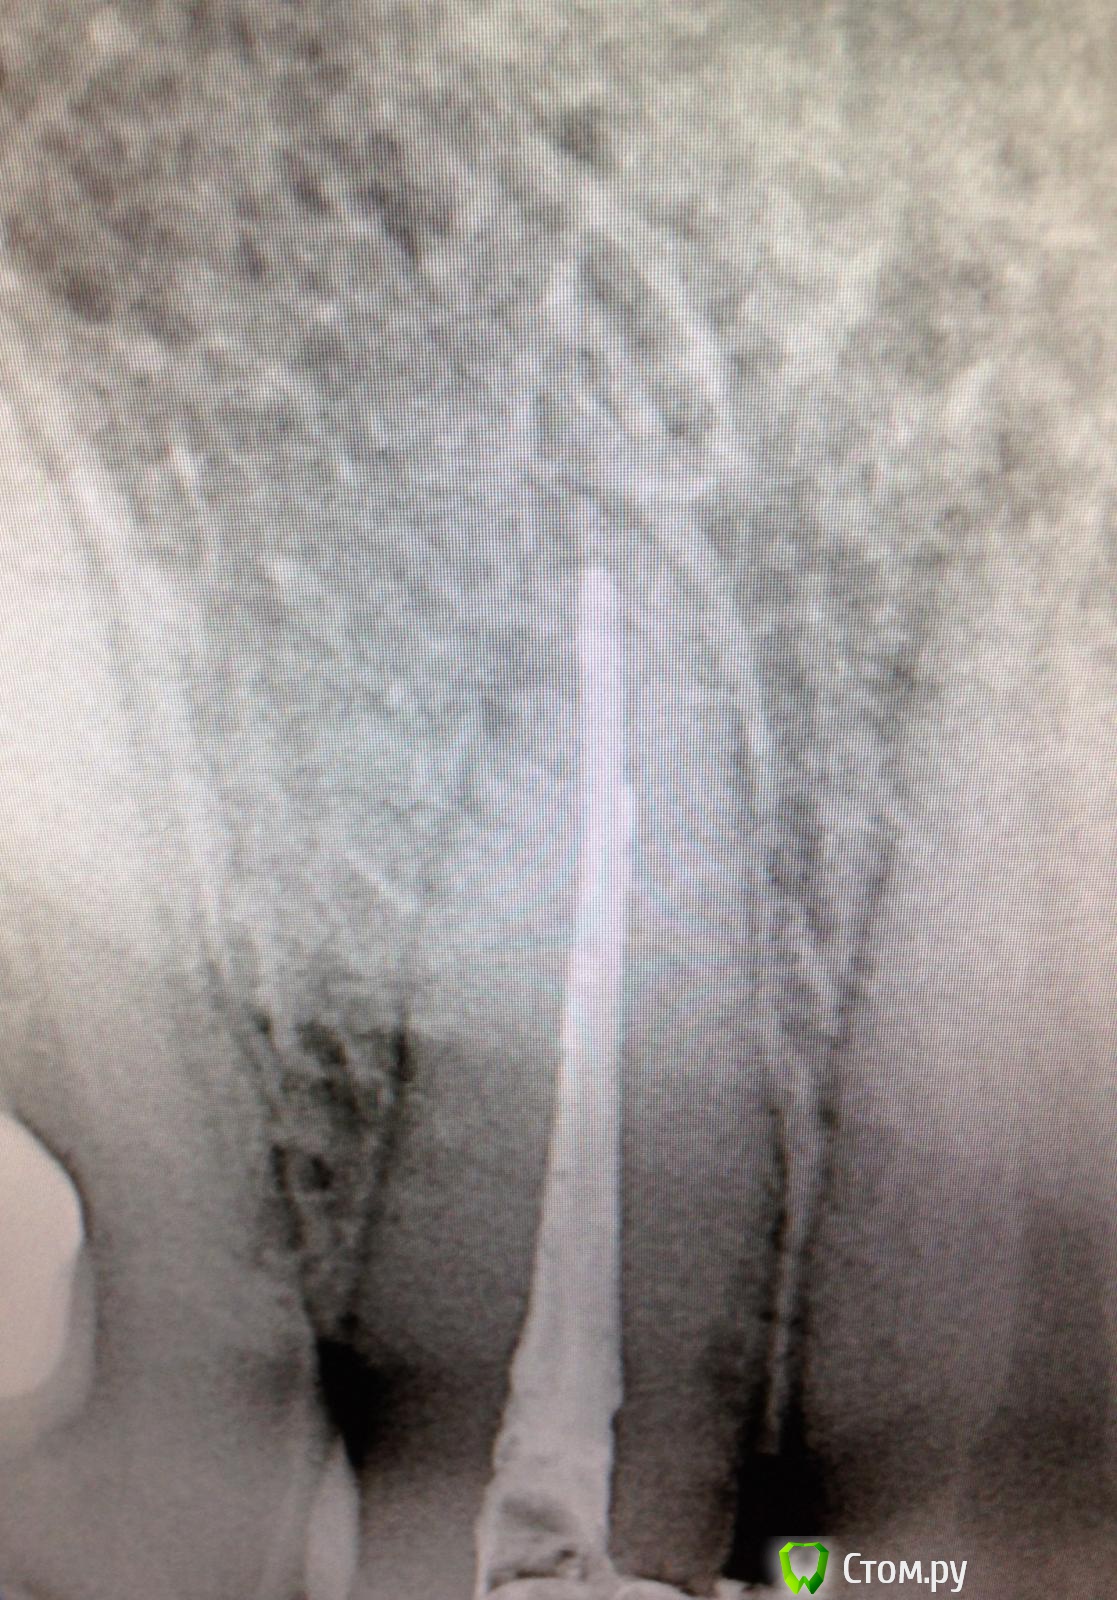

SSTi Опубликовано 6 сентября, 2014 Автор Поделиться Опубликовано 6 сентября, 2014 (изменено) Новая история.Пациент молодой.4 резца вч.12 периодонтит. 11 кариес дентина. 21, 22 - периодонтитСитуация до1 посещение. Анестезия 1.7 в области 21-22. Коффер. Преп. Обработка каналов. Ирригация. Кальций. Временная.2 посещение. Анестезия в области 11 ,12, 21 ,22. Коффер. Преп и реставрация 11.Преп, обработка и ирригация 12, паковка.Ирригация 21-22. При пошружении файла в каналы 21 и 22 - боль за 3-4 мм до апекса. Не кровит. Обработка была в пределах разумного(ленточное перфо не мог натереть). Идем на снимокБоль на этом уровне. Причем при введении мастер штифта боль есть. Если ввожу 15-20 аккуратно - боли нет. Добавляем анестезию. Аккуратно удается запломбировать 22.21 - боль осталась. Оставил кальций.На корнях 22 и 21 в боковом отделе есть разрежения небольшие. Боль примерно на их уровне. Но это вряд ли связано думаю. (Это латерали?).Вопрос. Какова причина боли? Склоняюсь к анестезии. Такое чувство, что повторно плохо взяла(посещения рядом по времени).+ слизистая вобл 21 была слабочувствительна Изменено 6 сентября, 2014 пользователем SSTi Ссылка на комментарий